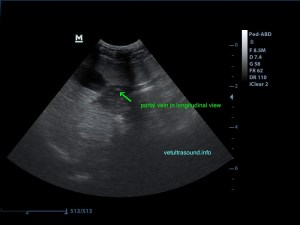

Αντίθετα στο τμήμα που δεν έχει γίνει εναπόθεση λίπους είναι εύκολη η απεικόνιση του τοιχώματος της πυλαίας φλέβας.

Δεν προκαλεί συμπίεση των γύρω ιστών ή αγγείων (mass effect) το υγιές τμήμα του ηπατικού παρεγχύματος.